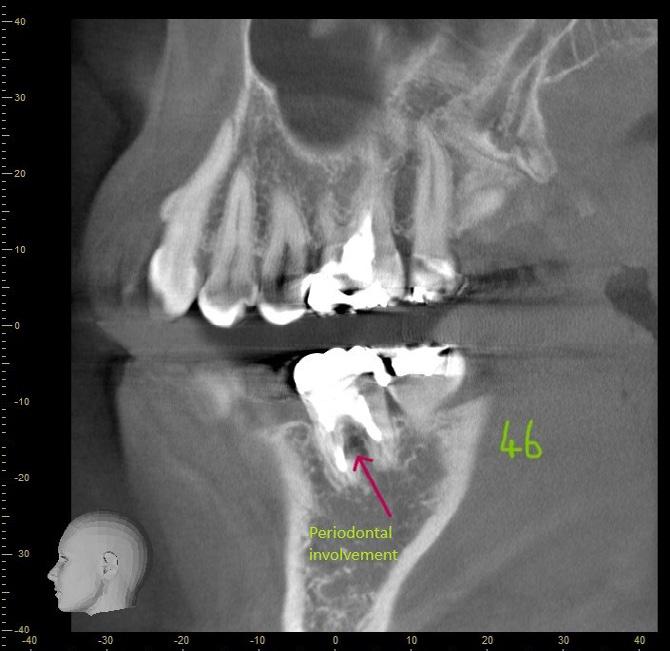

A 37-year-old female (Mrs H. K.) was referred for endodontic assessment and management of teeth 16, 26 and 46 before orthodontic space management. Clinical and radiographic evaluation, including CBCT scanning, revealed that teeth 16

and 26 were asymptomatic clinically; however, imaging confirmed the presence of missed mesiopalatal root canals, short obturation lengths in other canals, and distinct periapical radiolucencies. Both maxillary molars were diagnosed as previously root-filled with inadequate quality, exhibiting infected rootcanal systems (RCS), chronic apical periodontitis, and external apical inflammatory resorption associated with restoration breakdown, cracks, and recurrent decay. Tooth 46 shared similar diagnostic features but also demonstrated concurrent periodontal involvement, indicating a combined endodontic–periodontal lesion.

Case 1

Figure 1: CBCT sagittal section demonstrating periodontal bone loss involving the furcation area of tooth 46.

Figure 2: CBCT transverse section demonstrating bone loss involving the furcation area of tooth 46.